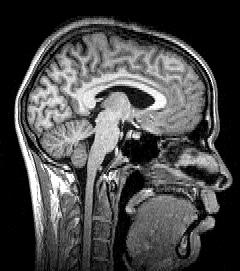

신경영상은 뇌의 구조와 기능을 시각적으로 보여주는 기술로, 19세기 이탈리아 신경과학자의 연구에서 시작되어 뇌혈관 조영술, 컴퓨터 단층 촬영(CT), 자기 공명 영상(MRI), 기능적 자기 공명 영상(fMRI) 등으로 발전해왔다. 현재는 구조적 뇌영상(CT, MRI)과 기능적 뇌영상(fMRI, PET, SPECT, MEG, EEG, DOI/DOT, EROS, fUS) 등 다양한 기술이 사용되며, 뇌졸중, 종양, 간질, 치매 등 신경학적 질환의 진단 및 치료에 활용된다.

뇌영상 기술은 크게 뇌의 구조를 보여주는 구조적 뇌영상과 뇌의 활동을 보여주는 기능적 뇌영상으로 나눌 수 있다.

뇌영상은 뇌의 구조와 기능을 연구하고 질병을 진단하는 데 사용되는 기술이다. 크게 뇌의 구조를 보여주는 구조적 뇌영상과 뇌의 활동을 보여주는 기능적 뇌영상으로 나눌 수 있다.구조적 뇌영상은 뇌의 해부학적 구조를 시각화하여 뇌종양과 같은 질병을 진단하는 데 사용된다.

3. 1. 2. 자기 공명 영상 (MRI)

자기공명영상(MRI)은 전리 방사선이나 방사성 추적자를 사용하지 않고, 자기장과 전파를 이용하여 뇌 구조를 고품질의 2차원 또는 3차원 영상으로 나타낸다. Magnetic resonance imaging|자기 공명 영상영어

자기 공명 영상의 핵심 아이디어는 순 자기화 벡터가 스핀 상태 간의 에너지 차이와 동일한 주파수의 에너지를 스핀 시스템에 노출시킴으로써(예: 무선 주파수 펄스) 이동될 수 있다는 것이다. 충분한 에너지가 시스템에 전달되면, 순 자기화 벡터를 외부 자기장의 것과 직각으로 만들 수 있다.

전체 온전한 뇌(사후)의 최고 공간 해상도 기록은 매사추세츠 종합 병원에서 2019년에 달성한 100마이크론이다.[13]